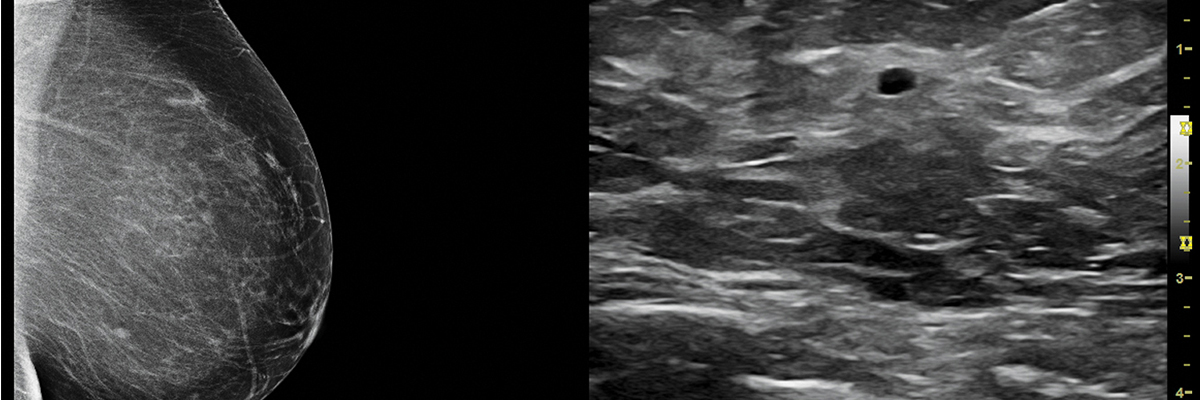

3D BREAST ULTRASOUND

One of the most promising new technologies is automated 3D ultrasound. Instead of flat, 2D images, this powerful ultrasound technology gives physicians a much more realistic view of the whole breast and its physical structures; providing multiple views — side to side, backand front and more.

Ultrasound evaluation of breast lesions is quick, inexpensive, and does not expose you to potentially harmful ionizing radiation.

scheduling

3D Breast Ultrasound is performed in our Port St. Lucie office only and must be scheduled. This exam can take up to 45 minutes.